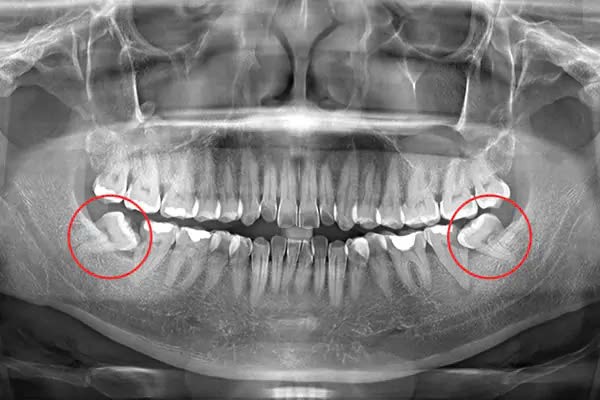

- Răng khôn mọc lệch, mọc ngầm: Khi răng khôn mọc lệch, đâm vào răng số 7, gây đau nhức, viêm nhiễm, ảnh hưởng đến các răng xung quanh.

- Mọc lệch, mọc ngầm: Trường hợp răng khôn mọc lệch, đâm vào răng bên cạnh hoặc mọc ngầm, cơn đau có thể dữ dội hơn và kéo dài hơn, có thể từ vài tuần đến vài tháng, thậm chí là tái phát nhiều lần trong suốt quá trình răng mọc lên hoàn toàn.